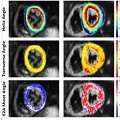

Characterizing cardiac involvement in amyloidosis using cardiovascular magnetic resonance diffusion tensor imaging

Alexander Gotschy, et al.

Published on: 5 September 2019